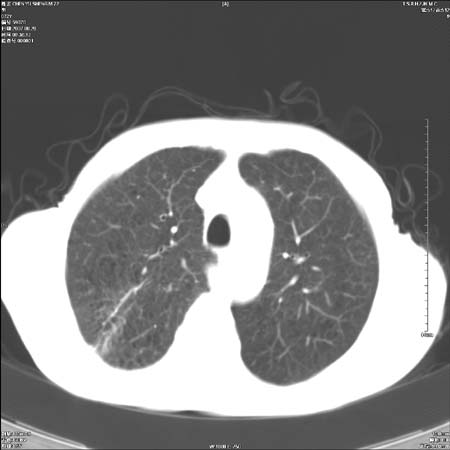

男性,72岁,既往肺结核,今复查。无前片对比。

纵隔窗

右侧中央型肺癌伴中叶不张可能性大,建议增强扫描.右上肺陈旧性肺结核.慢性支气管炎伴肺气肿.右侧少量胸腔积液.

右侧中央型肺癌伴中叶不张可能性大,建议纤支镜检查.右上肺陈旧性肺结核.肺气肿。

典型右肺中心型肺癌

右侧中央型肺癌伴肺不张可能性大,建议增强扫描.右上肺陈旧性肺结核.慢性支气管炎伴肺气肿.右侧少量胸腔积液.

右肺中心型肺癌

右侧中央型肺癌.上肺陈旧性肺结核.

1右侧中央型肺癌伴中叶不张2右侧少量胸腔积液3右上肺陈旧性肺结核

1.右肺中心性肺癌并右肺中叶综合征2。右侧胸腔少量积液3。右肺上叶结核球已钙化,4。慢支伴肺气肿

右侧中央型肺癌伴中叶不张可能性大,建议纤支镜检查.右上肺陈旧性肺结核.肺气肿。

右侧中央型肺癌伴中叶不张可能性大,建议增强扫描.右上肺陈旧性肺结核.慢性支气管炎伴肺气肿.右侧少量胸腔积液.

右侧中央型肺癌伴中叶不张

右肺中央型肺癌伴右肺中叶不张。

右上肺陈旧性肺结核。

支持右肺中心型肺癌并中叶不张,右上肺陈旧性肺结核钙化,右侧少量胸腔积液。

支持右侧中央型肺癌伴中叶不张可能性大,建议增强扫描.右上肺陈旧性肺结核.慢性支气管炎伴肺气肿.右侧少量胸腔积液.

支持 1右侧中心型肺癌伴中叶不张2右侧少量胸腔积液3右上肺陈旧性肺结核4双肺局限性肺气肿

1,右侧中央型肺癌.

2,右上肺陈旧性肺结核.

1.右侧中央型肺癌伴中叶不张,建议纤支镜检查.

2.右上肺陈旧性肺结核.

3.肺气肿。

4.右侧少量胸腔积液.

右侧中央型肺癌伴中叶不张并纵隔淋巴结增大,建议增强扫描.右上肺陈旧性肺结核.慢性支气管炎伴肺气肿.右侧少量胸腔积液。

右肺中心型肺癌并肺不张,陈旧性肺tb.慢支,肺气肿.

陈旧性肺结核.慢性支气管炎伴肺气肿,中央型肺癌伴中叶不张。

右侧中央型肺癌伴中叶不张可能性大;右上肺陈旧性肺结核.慢性支气管炎伴肺气肿

陈旧性结核是存在,但真正致命的却是右侧中心型肺癌。